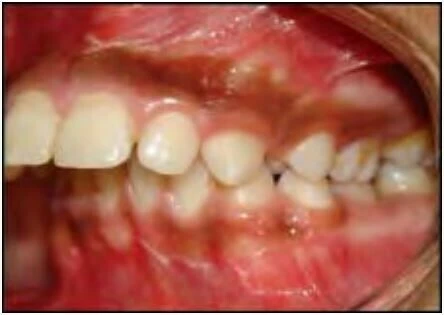

Cắn sâu

Với loại này, độ cắn phủ theo chiều dọc giữa răng hàm trên và răng hàm dưới lớn hơn so với bình thường.

Cắn hở

Với loại này thì không có độ phủ hoặc chỉ có một khoảng trống giữa các răng hàm trên và hàm dưới khi bệnh nhân cắn lại ở khớp cắn trung tâm. Một trường hợp cắn hở có thể gặp ở răng trước hoặc răng sau.